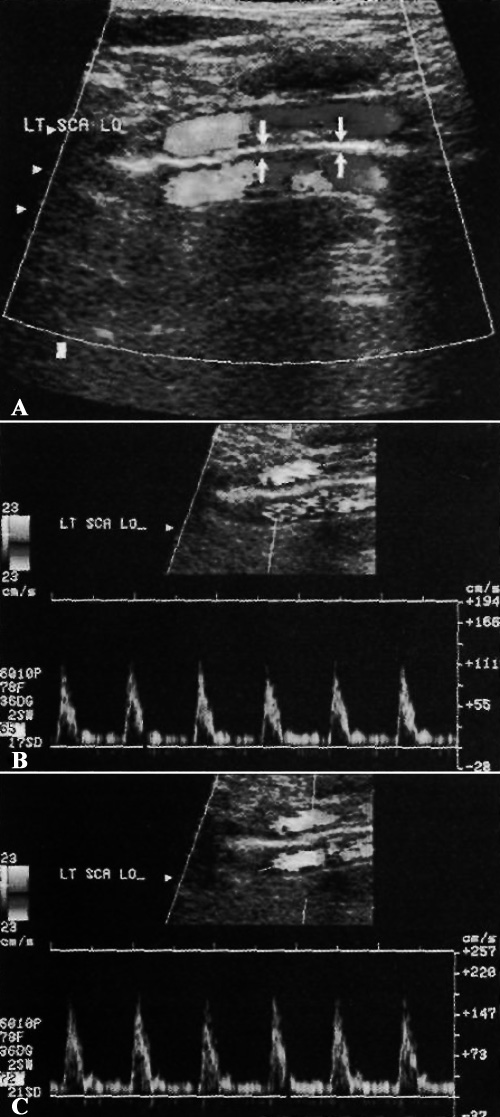

Допплерография подключичной артерии: артефакт зеркального изображения

Фото 9. Допплерография подключичной артерии: артефакт зеркального изображения. А – на допплерограмме визуализируется нормальная подключичная артерия, при этом наблюдается вторая аналогичная артерия под поверхностью плевры (см стрелки). В – спектральный допплеровский сигнал истинной артерии не отличается от сигнала отраженной (зеркальной) артерии (фото С)